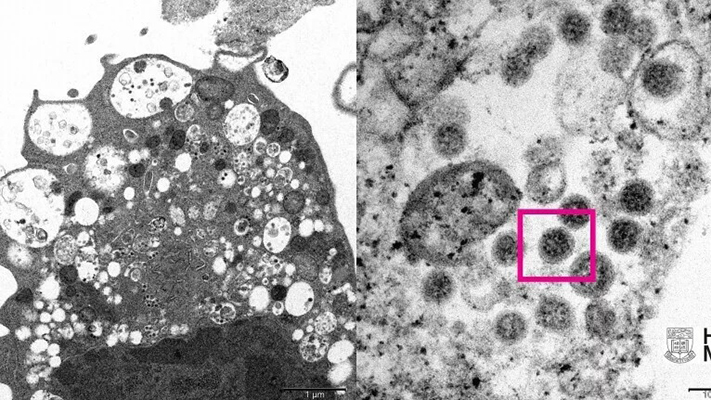

Medicinski naučnici, uključujući patologe i virologe, su uspjeli da naprave elektronski mikrograf bubrežne ćelije majmuna (Vero E6) nakon što je ona zaražena omikron varijantom novog koronavirusa. Pomenuti univerzitet je objavio fotografije omikrona s malim i velikim uvećanjem.

Pri malom uvećanju, slika pokazuje ćelijska oštećenja s nabreklim vezikulama koje u sebi sadrže male crne virusne čestice, pojasnili su naučnici.

Slika s velikim uvećanjem pokazuje gomile virusnih čestica sa šiljcima u obliku korone na njihovoj površini.